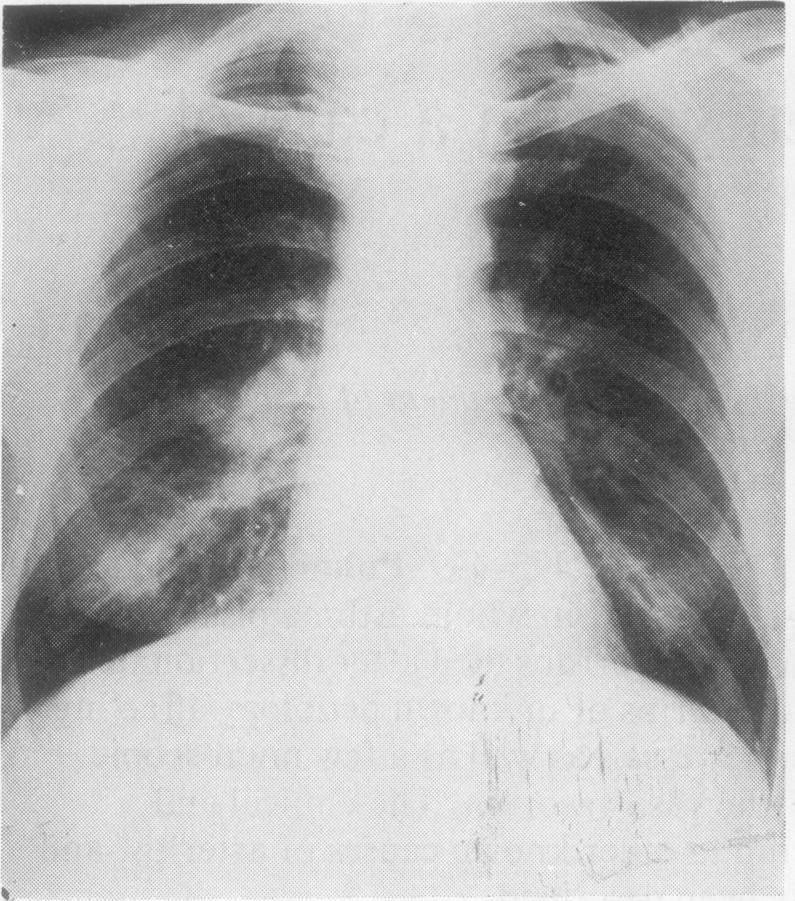

A patient in whom asthma preceded the development of multiple pulmonary and systemic artery aneurisms died after dissection of the aorta. At necropsy he was found to have widespread arteritis of unknown aetiology affecting many large and medium-sized pulmonary and systemic vessels as well as a few microscopic ones. Endarteritis obliterans was present in some of the vasa vasorum. The clinical and histopathological findings are discussed in relationship to other known causes of arteritis, and it is concluded that this condition has not previously been described.

一名哮喘先于多发性肺动脉和体动脉动脉瘤出现的患者,在主动脉夹层分离后死亡。尸检发现他患有病因不明的广泛性动脉炎,累及许多大中型肺动脉和体动脉血管以及一些微血管。一些血管滋养管存在闭塞性动脉内膜炎。结合动脉炎的其他已知病因对临床和组织病理学发现进行了讨论,得出的结论是这种情况以前未曾有过描述。